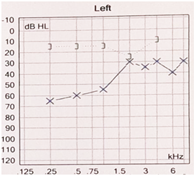

Para una evaluación diagnóstica precisa, es esencial realizar una audiometría en todos los pacientes (Fig. 3). Además, se recomienda realizar pruebas con diapasones de 256 Hz y 512 Hz.

Figura 3. Audiometría clásica de la otosclerosis. Hipoacusia conductiva, signo de cahart (Der) e Hipoacusia Mixta (Izq) |

En la audiometría, se observará una hipoacusia conductiva con el signo de Cahart, que se manifiesta como una caída en la vía ósea a la frecuencia de 2000 Hertz con mayor afectación en los tonos graves(Fig. 4). La timpanometría puede mostrar curva tipo A o As de Jerger, y se puede encontrar un reflejo estapedial ausente. En algunos casos, también puede existir hipoacusia mixta o neurosensorial.